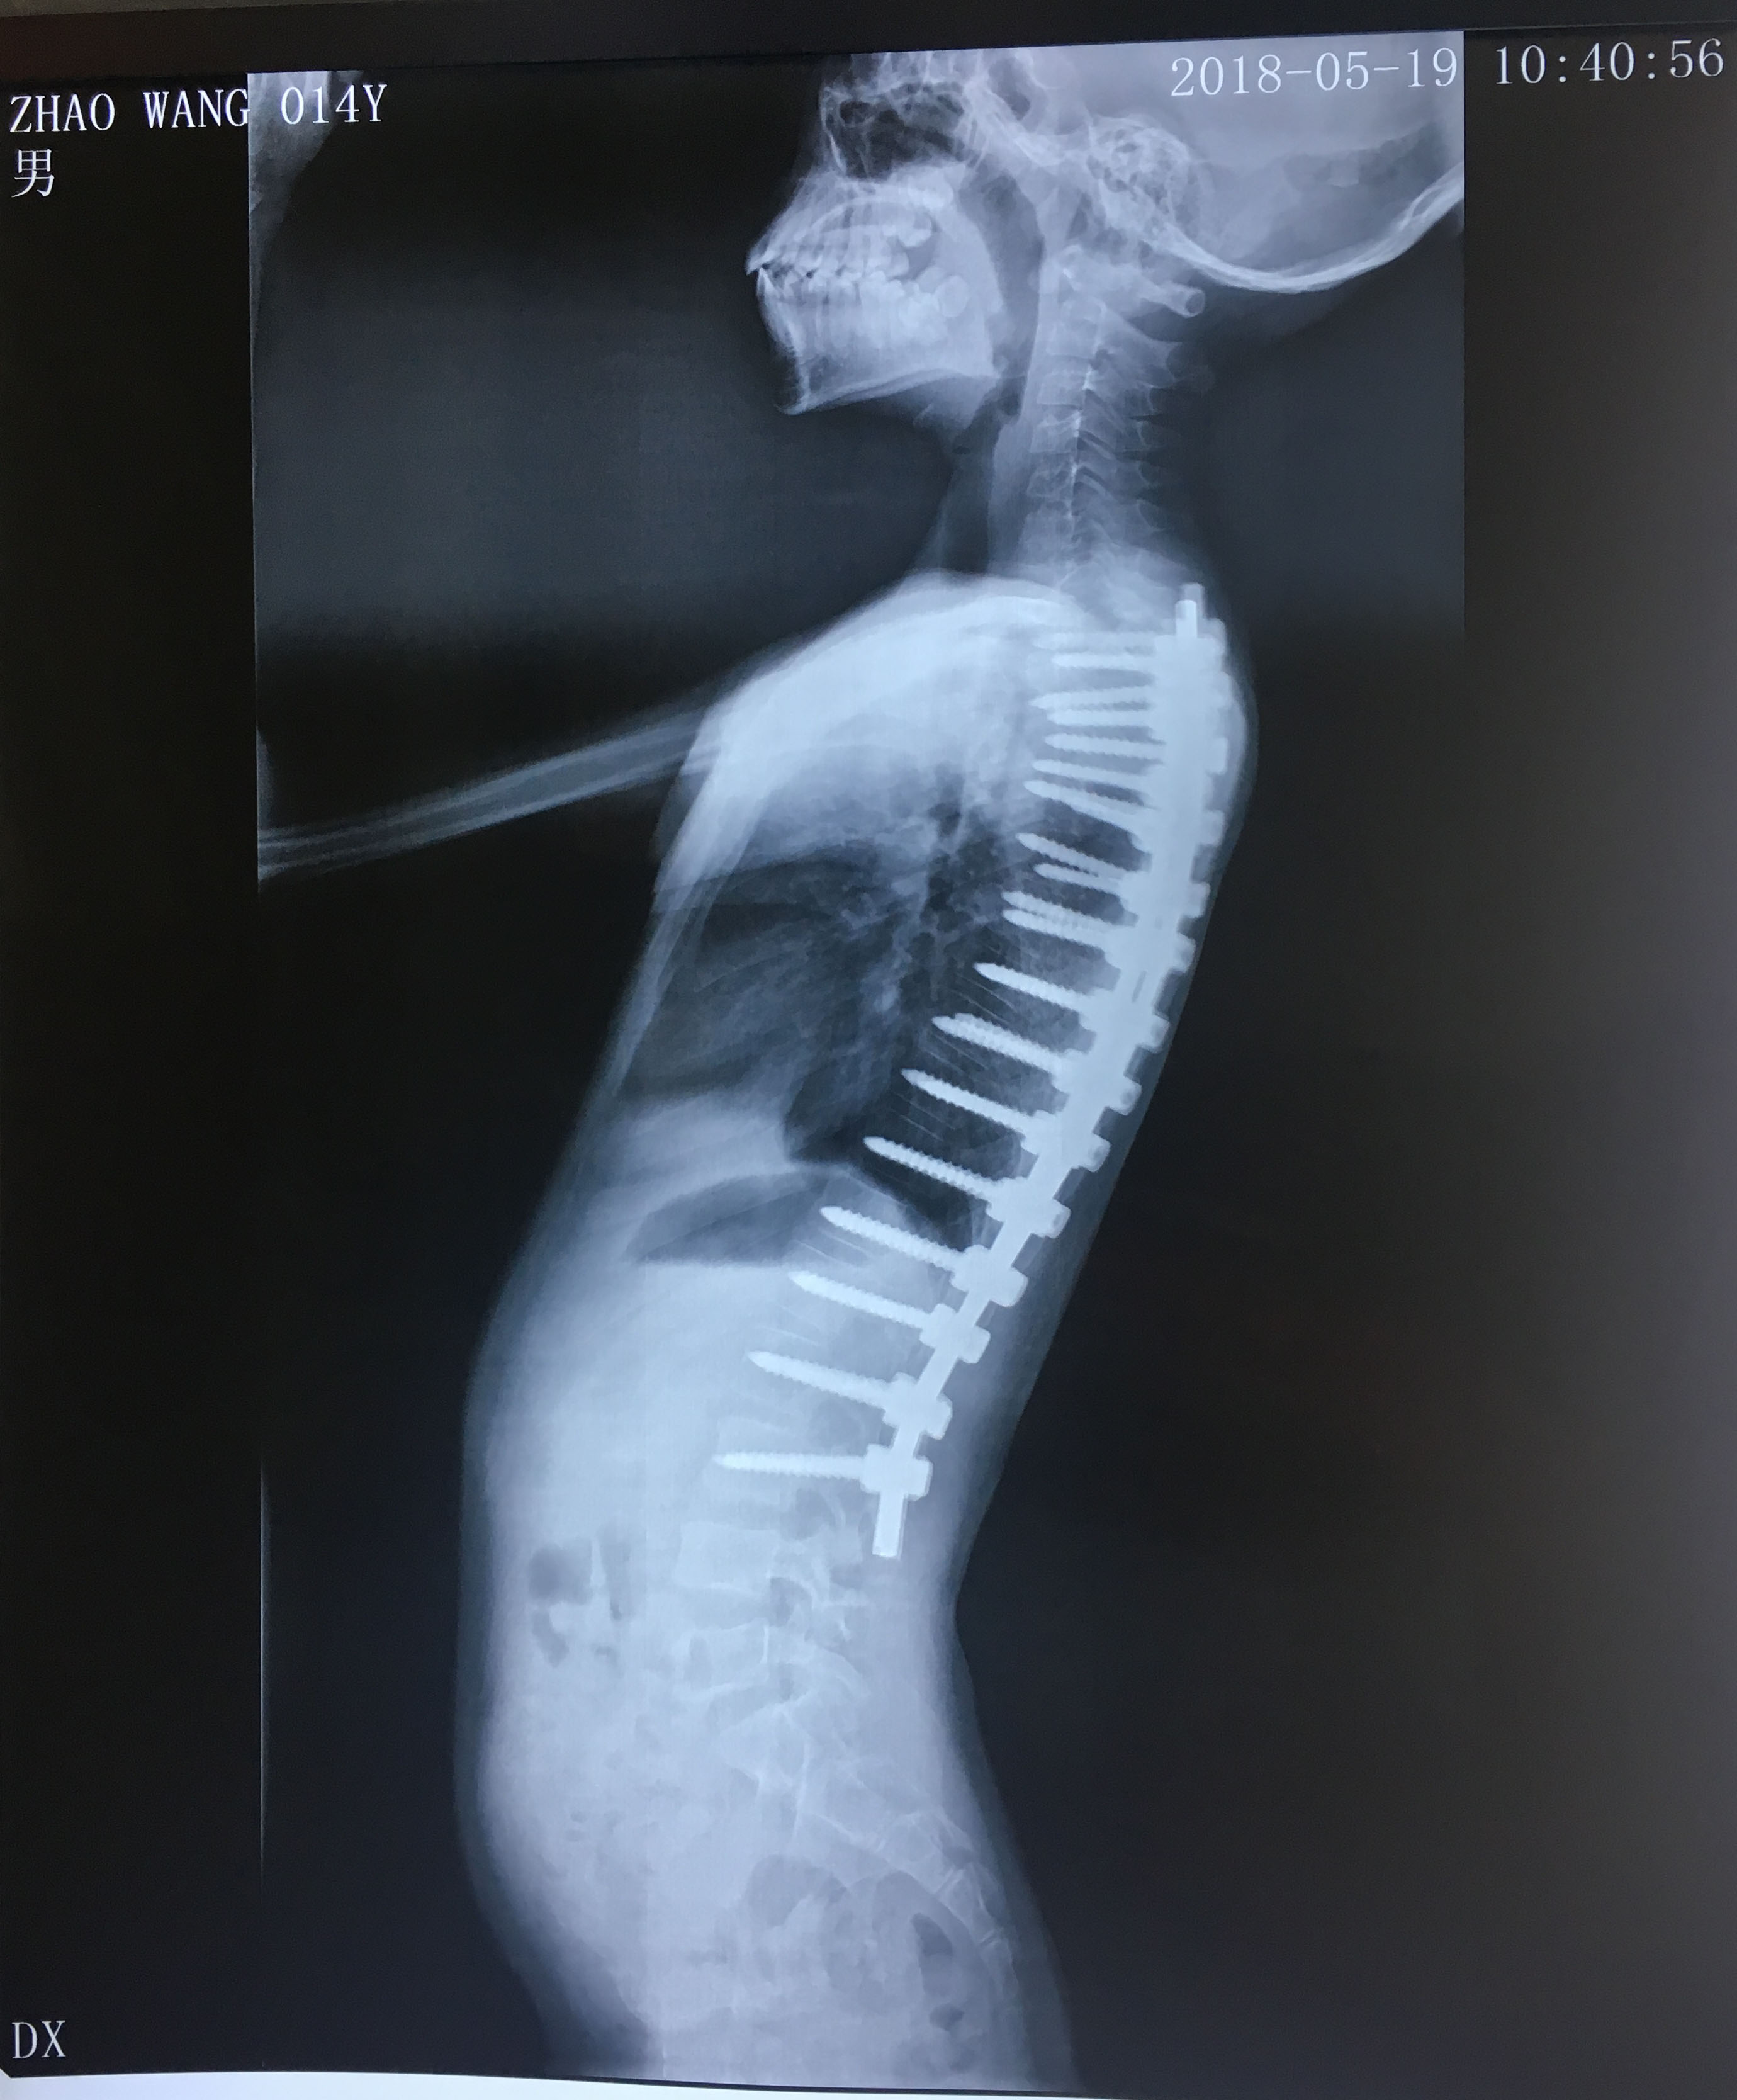

病例分享:脊柱后凸畸形矫形术

图片尺寸1376x641